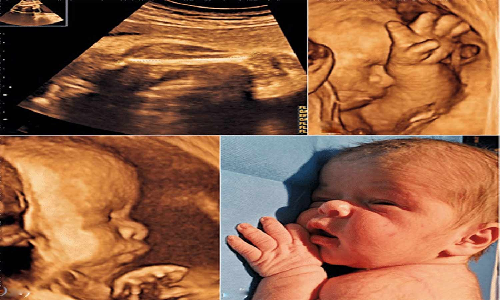

வேலூர் மாங்காய்மண்டி பகுதியை சேர்ந்தவர் கரண் (வயது 25). இவரது மனைவி சிவசக்தி. இவர் மக்கான் பகுதியில் உள்ள சுகாதார நிலையத்துக்கு பிரசவத்துக்காக நேற்று முன்தினம் அழைத்துச் சென்றனர்.

பின்னர் அவரை பென்லேன்ட் மருத்துவமனைக்கு அழைத்துச் சென்றனர். அவருக்கு குழந்தை இறந்து பிறந்தது. இந்த சம்பவம் வேலூரில் பரபரப்பை ஏற்படுத்தியது.

இதுகுறித்து மருத்துவ பணிகள் இணை இயக்குனர் கண்ணகி, சுகாதார பணிகள் துணை இயக்குனர் பானுமதி ஆகியோர் விசாரணை நடத்தி வருகின்றனர்.

இந்தநிலையில், குழந்தை இறந்ததற்கு ஆரம்ப சுகாதார நிலைய செவிலியர்களின் கவனக்குறைவு தான் என்று ஒருதரப்பினரும், பென்லேன்ட் மருத்துவமனையில் முறையாக பிரசவம் பார்க்க நடவடிக்கை எடுக்கப்படவில்லை என்று மற்றொரு தரப்பினரும் மாறிமாறி குற்றம் சாட்டி வருகின்றனர்.